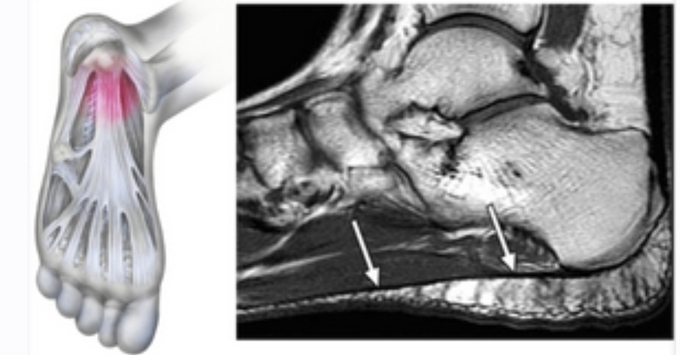

족저근막은 발바닥의 두꺼운 섬유질 막으로 발의 아치를 형성하고 걸을 때 발을 강력하게 지지해줍니다. 걸으면서 발뒤꿈치를 올리면 발뒤꿈치의 족저근막 부착 부위에 높은 장력이 가해집니다.

특히 달리기와 같은 활동 중에는 더 높은 장력이 가해져서 족저근막 부착 손상의 위험이 증가하게 됩니다. 족저근막염은 가벼운 부상이나 과도한 사용으로 인한 염증으로 발뒤꿈치와 발바닥에 통증을 일으키는 질환입니다. 아침에 일어나서 방바닥에 발을 딛는 순간 통증으로 깜짝 놀라는 경험을 해보신 적이 있다면 족저근막염 증상을 의심해봐야 합니다.

족저근막염은 외부 요인에 의해 갑자기 발생하는 것이 아니라 서서히 증상이 진행되는 것을 볼 수 있습니다. 발뒤꿈치 중앙보다 약간 앞으로 뻗어 있으므로 내측에서 발생하고, 아침에 일어나거나 오래 앉아 있다가 갑자기 일어날 때 강도가 높게 나타납니다. 잠을 자거나 앉는 것처럼 몸이 이완된 상태에서 움직이면 갑자기 늘어나 통증이 오게 됩니다.

통증은 일반적으로 발뒤꿈치 안쪽과 바닥에서 느껴집니다.

족저 근막염은 아침에 통증이 잘 생깁니다. 통증이 발생하는 원인은 수면 중에는 근막이 짧아지기 때문에 잠에서 깨어 걷게 되면 근막이 다시 늘어나면서 통증이 유발됩니다.